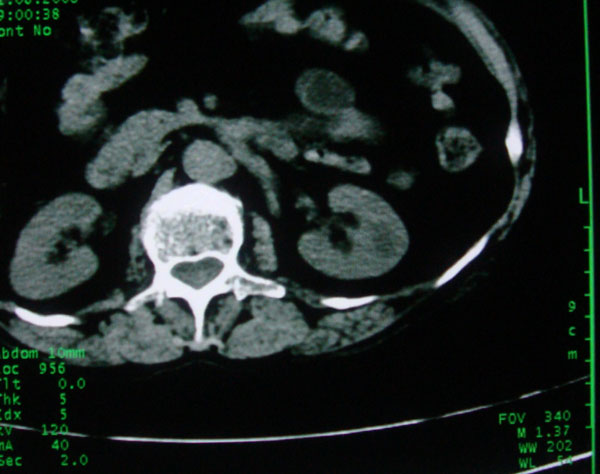

患者女性体查.发现左肾有低密度影,大家考虑是什么.其它方面没有什么异常.低密度影ct值约22hu.

左肾低密度影,境界尚清,查体发现,临床无其他首先考虑肾囊肿,如果增强一下对鉴别有帮助。

左肾不均匀低密度,其形态不规则、边界不清楚,更谈不上锐利。虽无局部凸出,但最后一张片显示仍有比较明显的隆起,我多考虑为肾癌,建议增强或mri检查。